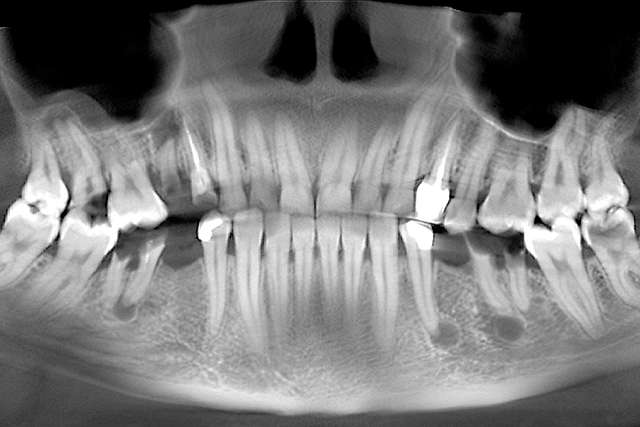

Implanturile dentare sunt tratamente indicate pentru dinti care nu mai sunt recuperabili. Implanturile au la baza lor principiul osteointegrarii, altfel spus, implantul se integreaza in os. Pentru o perioada lunga de timp, acesta a fost principalul obiectiv la nivel de industrie. Implantul sa fie integrat, sa fie plasat in functie de os. Astazi stim deja ca osteointegrarea este extrem de predictibilă si ne focusam pe alte elemente cheie care fac diferenta in calitate la un dinte restaurat cu implant dentar.

Chirurgia ghidata, ne faciliteaza o pozitie ideal pre-planificata, care nu tine cont doar de os, ci si de o pozitie optima in relatie cu viitorul dinte.Chirurgia ghidata înseamnă o precizie crescuta, care inseamna siguranta mai mare, timp operator mai scazut, si trauma mai mica. De asemenea focusul in acest tip de interventii a migrat spre reconstructia tesuturilor, care e pe termen lung are un impact mult mai mare atat estetic cat si biologic, inserarea implantului in sine fiind trivializata de folosirea ghidului chirurgical. Cazul de fata este un exemplu al acestui tip de abordare.